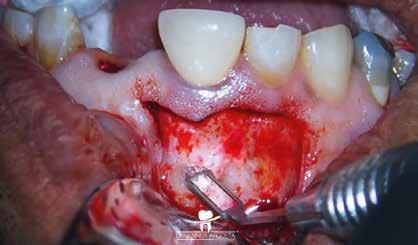

Egy 38 éves nőbeteg a korábban kezelt jobb felső második kisőrlőfogából (1.5) kiinduló mérsékelt fájdalom miatt jelentkezett rendelésünkön. A kórtörténetében jelen panasza szempontjából releváns információ nem szerepelt. A beteg a klinikai vizsgálat során vertikális kopogtatásra enyhe érzékenységet jelzett. A kérdéses fog körül mérhető szondázási mélység és a fogmobilitás fiziológiás volt. Periapicalis röntgenfelvételen egy, a fog gyökércsúcsán túl presszálódott betört gyökérkezelő műszerből származó eszközfragmentumot láttunk (2. a. ábra). A preoperatív CBCT-felvétel a buccalis csontlemez épségét igazolta (2. b-c. ábra). A fog revíziója öt hónappal korábban történt. A már előzőleg gyökérkezelt, gyökértömött, majd revideált 1.5-ös fog esetében a diagnózisunk periodontitis periapicalis symptomatica volt. A periapikális elváltozás kezelése érdekében navigált endodonciai mikrosebészeti beavatkozást végeztünk.

A felső állcsontról intraorális szkent (TRIOS) készítettünk, és az ezáltal kapott STL fájlt (2. d. ábra) a CBCT-felvétel során nyert DICOM fájlokkal a Zirkonzahn.Implant-Planner (Zirkonzahn) szoftverben egyesítettük. A sebészi sablont ebben a programban megterveztük, majd a Meshmixer (Autodesk) szoftver se-

gítségével tovább módosítottuk. Az így kapott sebészi sablon egyértelműen meghatározta a periapikális terület eléréséhez szükséges csontablak határait (2. e-f. ábra) Helyi érzéstelenítést követően teljes vastagságú mucoperiostealis lebenyt képeztünk, majd a buccalis csont feltárását követően (2. g. ábra) a sablon segítségével bejelöltük a preparálandó csontablak határait (2. h. ábra). A csontablak kialakítása során Piezotome CUBE LED kézi-darabot alkalmaztunk, majd a leemelését követően a betört eszközt megkerestük (2. i. ábra) és eltávolítottuk (2. j. ábra). A rezekciót ultrahangos megmunkáló fejekkel (ACTEON) végeztük, majd retrográd preparáció következett.

A retrográd gyökértömés elkészítése során TotalFill BC RRM Fast Set Putty-t (FKG) használtunk (2. k. ábra). A lebeny széleit 5/0-s Prolene varratokkal egyesítettük (2. l. ábra). A varratok a műtétet követően 72 órával kerültek eltávolításra. A beteg két évvel később kontrollröntgen készítése céljából érkezett rendelőnkbe. A vizsgálat során a fog tünetmentesnek és funkcióképesnek bizonyult (2. m. ábra).